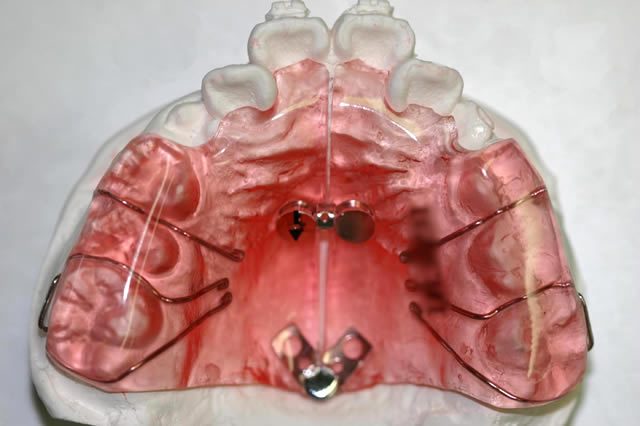

歯列の幅が狭い時に、適切なスペースを作る装置で主に歯を側方に押し広げます(広げる幅は内部のネジで調節)。患者さまによっては、永久歯に生えそろった後、第2期治療としてワイヤーを用いて全体の歯並び・咬み合せの治療を行います。